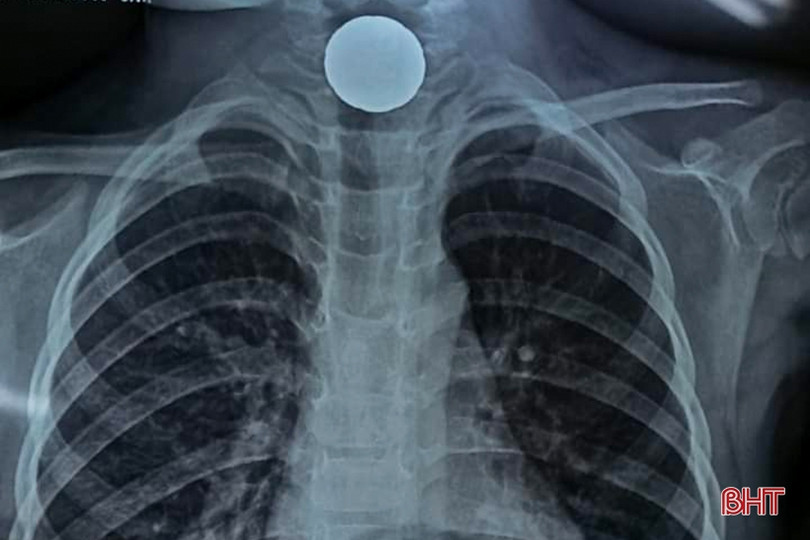

Hình ảnh đồng xu mắc tại thực quản qua phim chụp X.Quang.